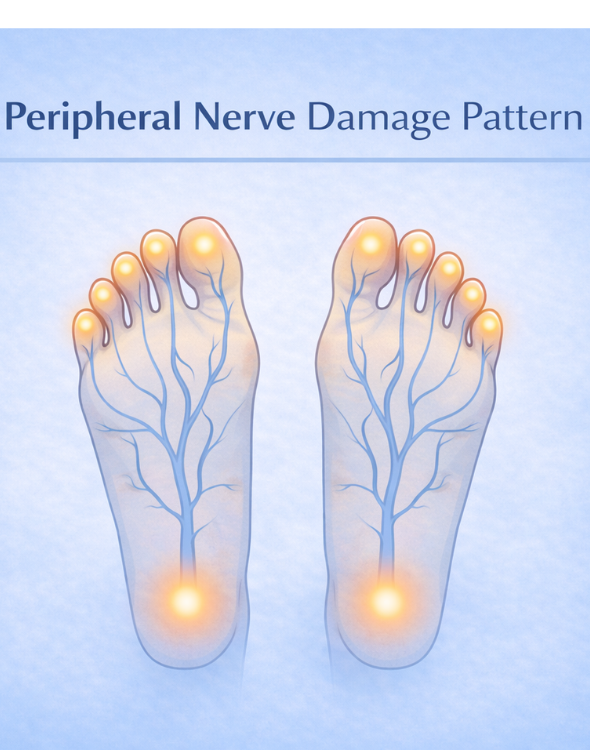

In many situations, diabetic neuropathy primarily affects nerves in the feet and legs first. As a result, early sensory changes may often begin in these areas. As nerve signals gradually change, people may therefore notice numbness, tingling, or reduced sensitivity in these areas.

Symptoms of diabetic neuropathy often begin in the feet. For example, tingling or numbness may first appear in the toes or soles. In addition, some individuals may notice burning sensations or reduced sensitivity to temperature. As a result, these sensory changes may gradually become more noticeable during daily activities. Consequently, early patterns in nerve sensation may become easier to observe over time.

As nerve function gradually changes, balance and coordination may also be affected. Consequently, some individuals may notice subtle differences in walking patterns or muscle control. Consequently, people may begin to notice subtle changes in walking patterns or muscle control over time. Meanwhile, sensory changes in the feet may continue to develop gradually. Your Attractive Heading